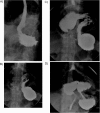

Presentation of case: We report the case of a 61 year old, healthy male, referred to surgical consultation complaining of epigastric discomfort and postprandial fullness. The diagnostic workup showed a mesentero-axial volvulus of the stomach. He was operated electively: reduction of volvulus, Nissen fundoplication and gastropexy was performed, with resolution of symptoms.